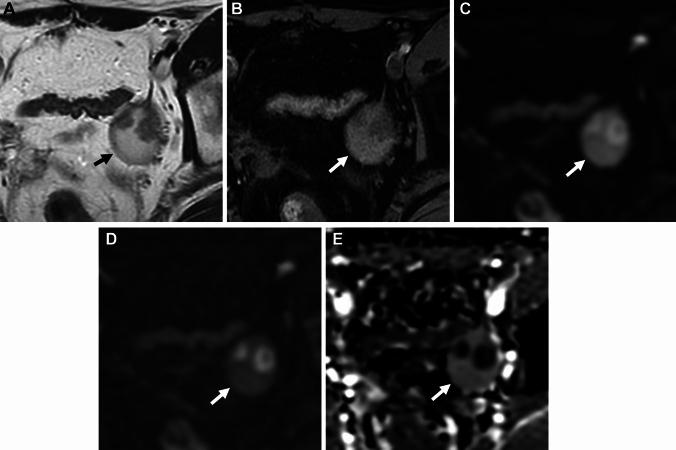

Endometriosis is a benign, common, but controversial disease due to its enigmatic etiopathogenesis and biological behavior. Recent studies suggest multiple genetic, and environmental factors may affect its onset and development. Genomic analysis revealed the presence of cancer-associated gene mutations, which may reflect the neoplastic aspect of endometriosis. The management has changed dramatically with the development of fertility-preserving, minimally invasive therapies. Diagnostic strategies based on these recent basic and clinical findings are reviewed. With a focus on the presentation of clinical cases, we discuss the imaging manifestations of endometriomas, deep endometriosis, less common site and rare site endometriosis, various complications, endometriosis-associated tumor-like lesions, and malignant transformation, with pathophysiologic conditions.